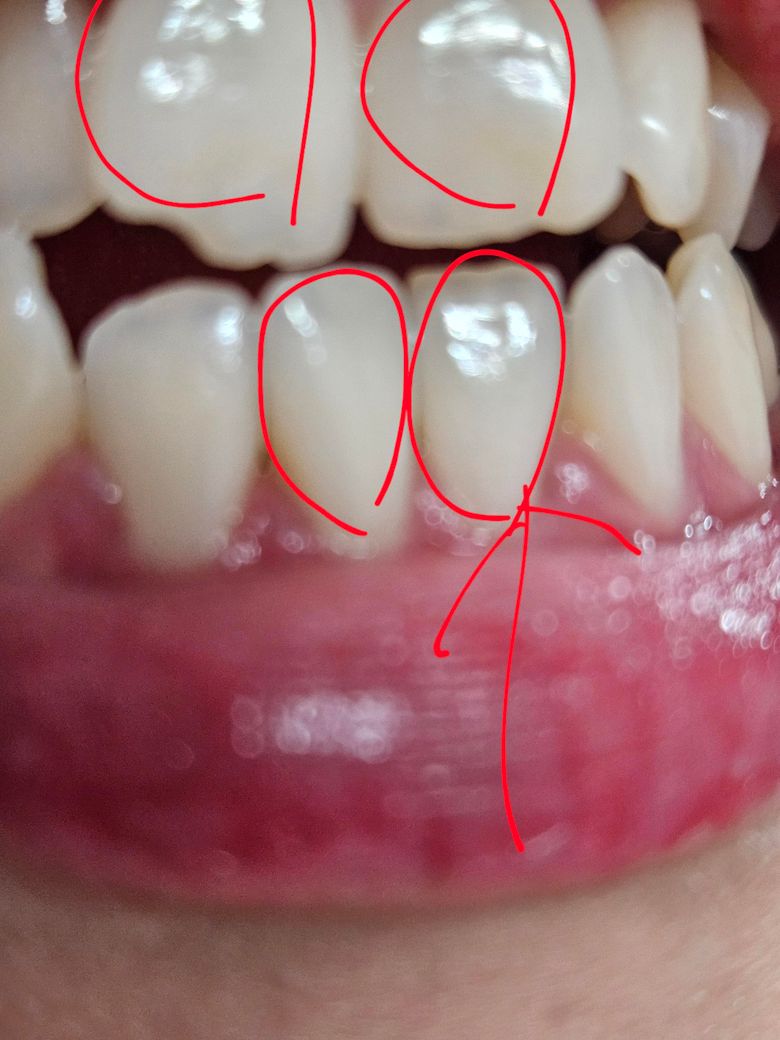

자연치아 앞니 우둘투둘.....원인, 대처방안

동그라미 치아 앞 표면이 우둘투둘해요...

원래 안그랬는데 큐라덴 5460 사용해서 바스법으로 양치했는데 저래 됐어요.. 원래는 매끈했는데 혀로 느껴집니다. 부드러운 칫솔이라해서 사용했는데 치아가 갈린걸까요?

사진상으로 봤을때는 문제가 없어보입니다.

치아는 원래 평평한 면이 아니라 융선과 구라는 해부학적 구조물이 있오 굴곡이 있는데요. (구글에 중절치 해부학적구조 검색해보시면 도움이 될 것 같습니다.) 우둘투둘하다고 하시는게 거칠다는게 아니라 굴곡이 있다는 말씀이시면 정상입니다. 약한 칫솔로 마모가 발생해서 우둘투둘해질수는 없고 거칠다면 다른 원인이 있을 것으로 보입니다.

일단 거친게 아니고 그냥 굴곡이 있다 정도라면 정상적인 구조이니 너무 신경쓰지는 않으셔도 되겠습니다.